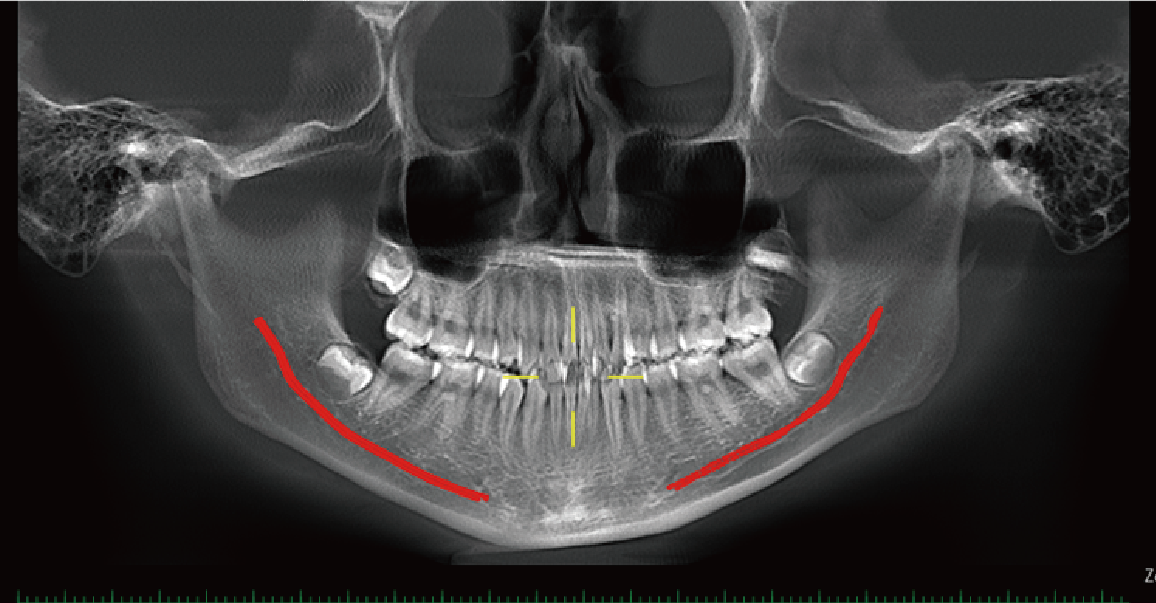

Neural Tube Automatic Labeling

Label the neural tube automatically in the CT image, providing great convenience for diagnosis.